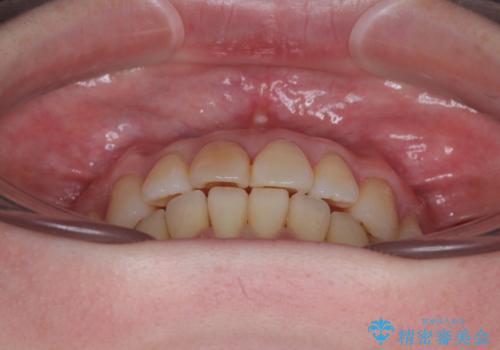

前歯のデコボコをインビザライン・モデレートで矯正治療

- 上下前歯のデコボコを気にして来院された患者様です。

安価なインビザラインパッケージを用いての治療を希望されており、デコボコの程度が中等度であったため、インビザライン・モデレートを用いて矯正治療を行うこととしました。

インビザライン・モデレートは、製作できるアライナーの枚数に制限があるため、移動可能な量に限りがあるものの、インビザライン・ライトよりも枚数が多いため、幅広い症例に対応可能です。